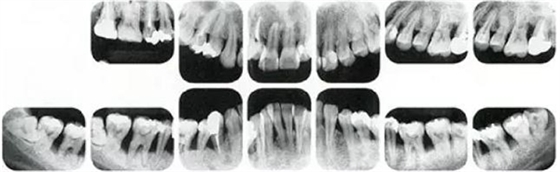

①的患者是35歲女性。4~10mm的牙周袋和大量的牙石。特別是在左上、右下、左下的磨牙處能看到大量牙槽骨吸收。這名患者是慢性牙周炎,僅在磨牙處有局部由風(fēng)險(xiǎn)因子導(dǎo)致(解剖學(xué)形態(tài))導(dǎo)致的重度病癥發(fā)展。

另一方面25歲女性的參考病例

②將會(huì)是什么樣的呢?左上、右下、左下的磨牙處有大量牙槽骨吸收,考慮到其發(fā)病年齡,斷定為是侵襲性牙周炎局部型。

●參考病例① 35歲女性

35歲女性。妊娠4個(gè)月。過(guò)去雖然接受過(guò)刷牙指導(dǎo),但菌斑控制狀態(tài)依然不理想?;颊哂邪l(fā)現(xiàn)自己刷牙時(shí)牙齦出血。

●參考病例② 25歲女性

25歲女性。菌斑控制狀態(tài)不好。齦溝除磨牙處外全在3mm以下,X光照片上左上、右下、左下的第一磨牙上有垂直性骨吸收。這個(gè)病例是參考病例①10年前的狀態(tài),是典型的侵襲性牙周炎局部型。